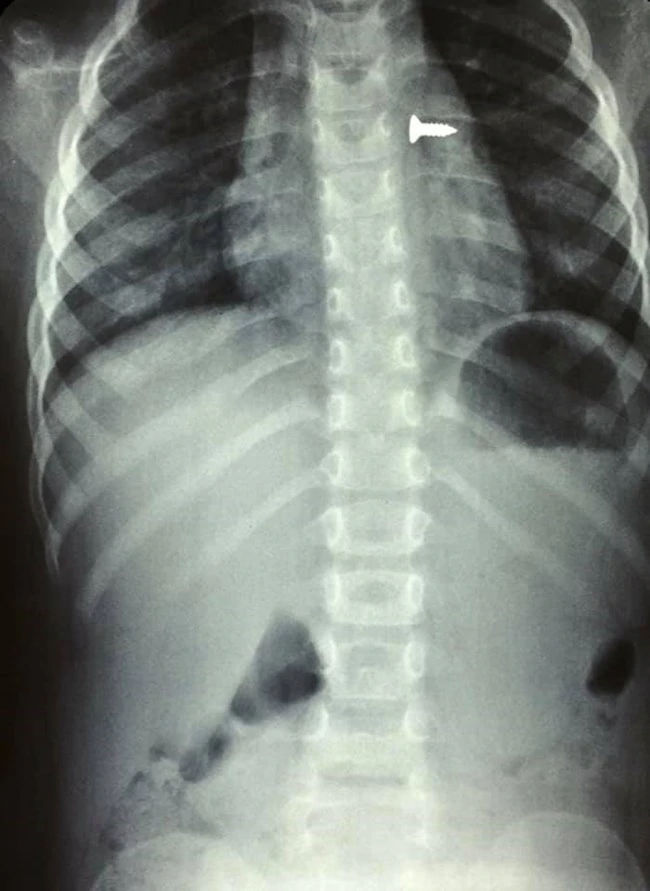

Σοκ προκαλούν οι ακτινογραφίες από ένα κοριτσάκι στην Κρήτη, που κατάπιε βίδα, η οποία κατέληξε στον αριστερό του πνεύμονα.

Αμέσως του έγιναν ακτινογραφίες που έδειξαν πως η βίδα βρισκόταν στον αριστερό πνεύμονα του παιδιού.